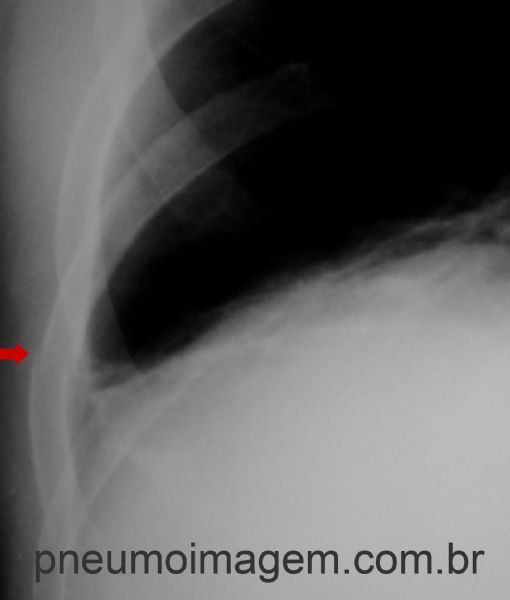

Também havia fratura no 9º arco costal à esquerda. Observe o desalinhamento entre as corticais ósseas.

Chaves: Fracture in the 9th rib on the left.